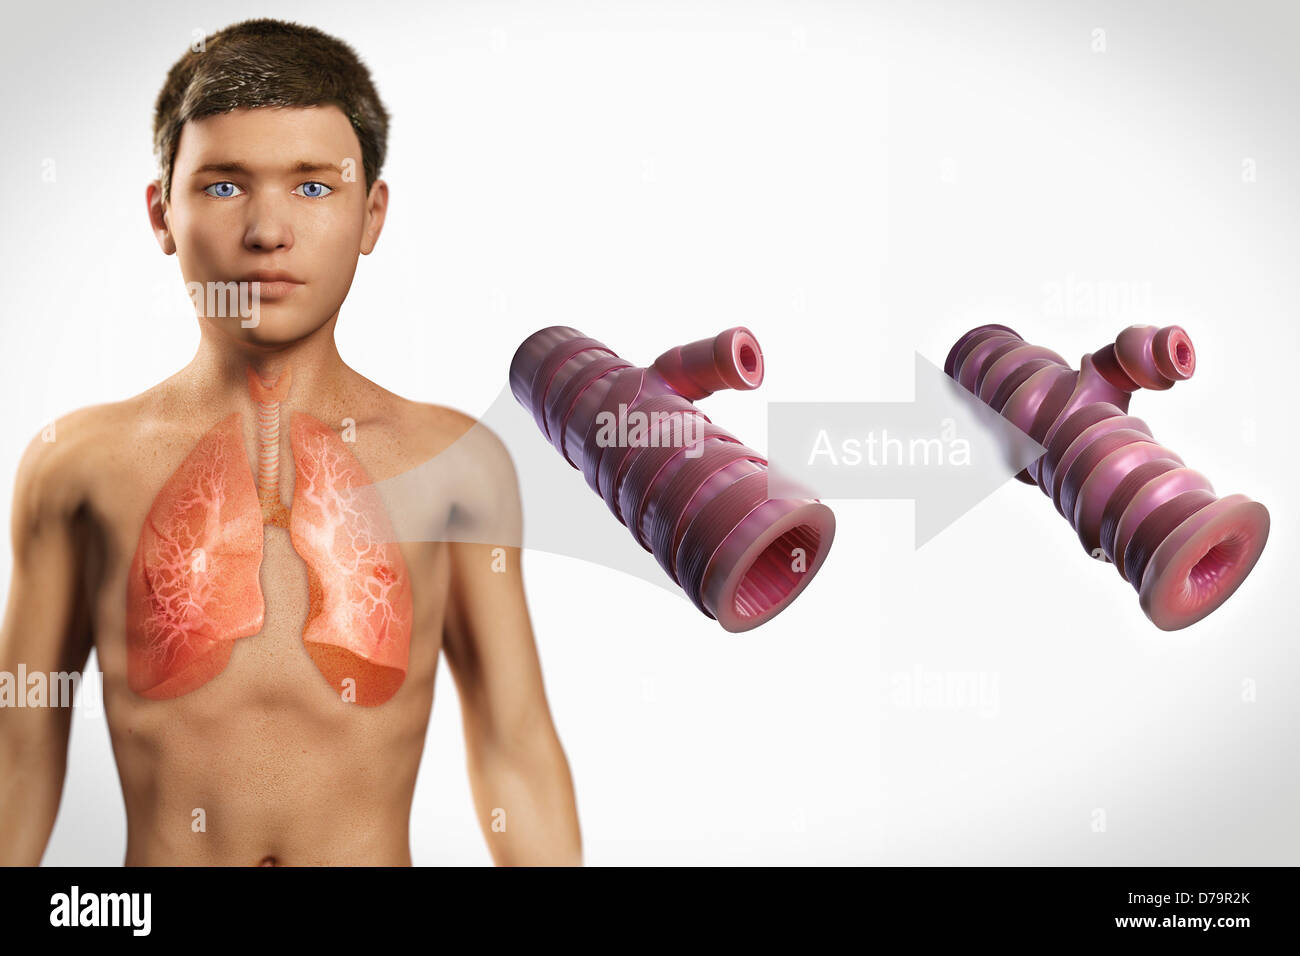

Asthmatic Airway Stock Photohttps://www.alamy.com/image-license-details/?v=1https://www.alamy.com/stock-photo-asthmatic-airway-56149201.html

Asthmatic Airway Stock Photohttps://www.alamy.com/image-license-details/?v=1https://www.alamy.com/stock-photo-asthmatic-airway-56149201.htmlRMD79PTH–Asthmatic Airway

Asthmatic Airway Stock Photohttps://www.alamy.com/image-license-details/?v=1https://www.alamy.com/stock-photo-asthmatic-airway-56149109.html

Asthmatic Airway Stock Photohttps://www.alamy.com/image-license-details/?v=1https://www.alamy.com/stock-photo-asthmatic-airway-56149109.htmlRMD79PN9–Asthmatic Airway

Asthmatic Airway Stock Photohttps://www.alamy.com/image-license-details/?v=1https://www.alamy.com/stock-photo-asthmatic-airway-56149136.html

Asthmatic Airway Stock Photohttps://www.alamy.com/image-license-details/?v=1https://www.alamy.com/stock-photo-asthmatic-airway-56149136.htmlRMD79PP8–Asthmatic Airway

Asthmatic Airway Stock Photohttps://www.alamy.com/image-license-details/?v=1https://www.alamy.com/stock-photo-asthmatic-airway-56149371.html

Asthmatic Airway Stock Photohttps://www.alamy.com/image-license-details/?v=1https://www.alamy.com/stock-photo-asthmatic-airway-56149371.htmlRMD79R2K–Asthmatic Airway